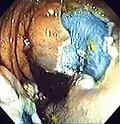

Colonoscopy (/ˌkɒləˈnɒskəpi/) or coloscopy (/kəˈlɒskəpi/)[1] is a medical procedure involving the endoscopic examination of the large bowel (colon) and the distal portion of the small bowel. This examination is performed using either a CCD camera or a fiber optic camera, which is mounted on a flexible tube and passed through the anus.[2][3]

The purpose of a colonoscopy is to provide a visual diagnosis via inspection of the internal lining of the colon wall, which may include identifying issues such as ulceration or precancerous polyps, and to enable the opportunity for biopsy or the removal of suspected colorectal cancer lesions.[4][5]